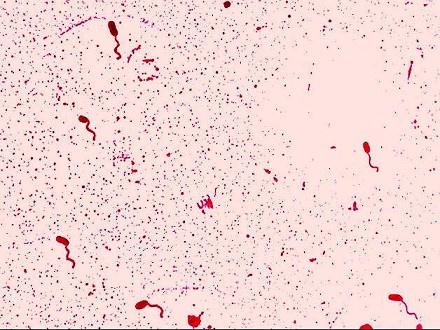

问题 关于图中所示的霍乱弧菌,叙述正确的是 ( )

选项 A.霍乱弧菌释放的内毒素是引起腹泻的主要因素 B.霍乱弧菌不发生变异 C.霍乱肠毒素(CTX)耐热 D.霍乱弧菌对热和消毒剂均敏感 E.霍乱弧菌在鱼虾或贝壳生物中不能生存

答案 D